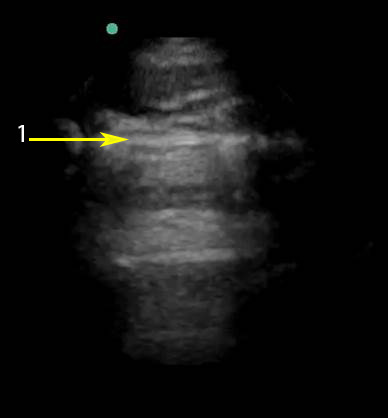

Imagen 2 de la evaluación de la pleura pulmonar

Línea pleural